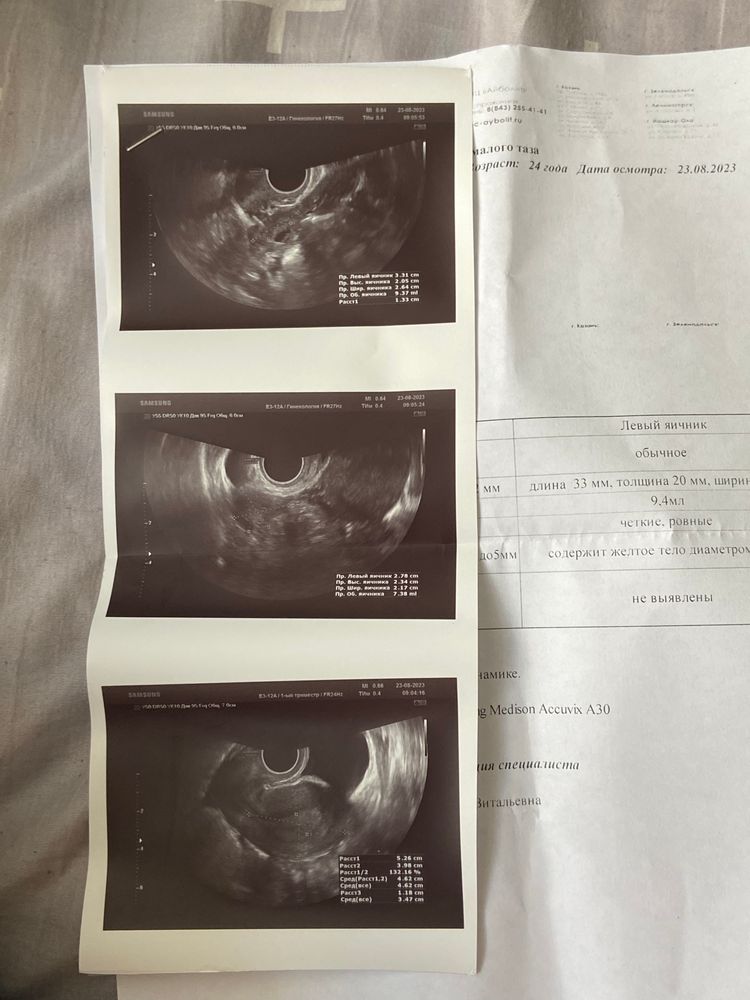

Девочки доброе утро, утром сдала хгч, и пошла прием к гинекологу, она пощупала меня и сказала примерно 5 недель, и сделала узи, по узи как все и говорили ничего не видно, говорит что плодное яйцо видимо не спустилась, назначила сделать хгч через два дня и во вторник перед следующем узи, через неделю записалась на повторное узи 🙏🏻

Обожаю эти умозаключения врачей не опустилось пя😒.. если матка на 5 недель, значит растет .. хгч начинает когда пя хоть где то прикрепляется .. у вас наверное поздняя овуляция поэтому еще рано чтобы увидеть его в матке , хгч сдавайте в динамике, если рост хороший то на узи можно и через две недели, если плохой рост и не дай бог выделения и боли то узи в динамике для исключения внематочной